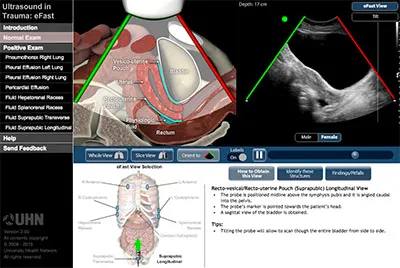

eFAST (Extended Focused Assessment with Sonography for Trauma)

- Views: Pericardial (subxiphoid), RUQ (hepatorenal), LUQ (splenorenal), Pelvic (suprapubic), Anterior thoracic (lung sliding).

- Detects: Free fluid (pericardial, pleural, peritoneal, pelvic), pneumothorax.

- 📌 Mnemonic (FAST views): "Right Upper, Left Upper, Pelvic, Cardiac" (RUQ, LUQ, Pelvic, Subxiphoid).

⭐ eFAST: High specificity (95-100%) for intraperitoneal free fluid (detects ≥100-200 ml).